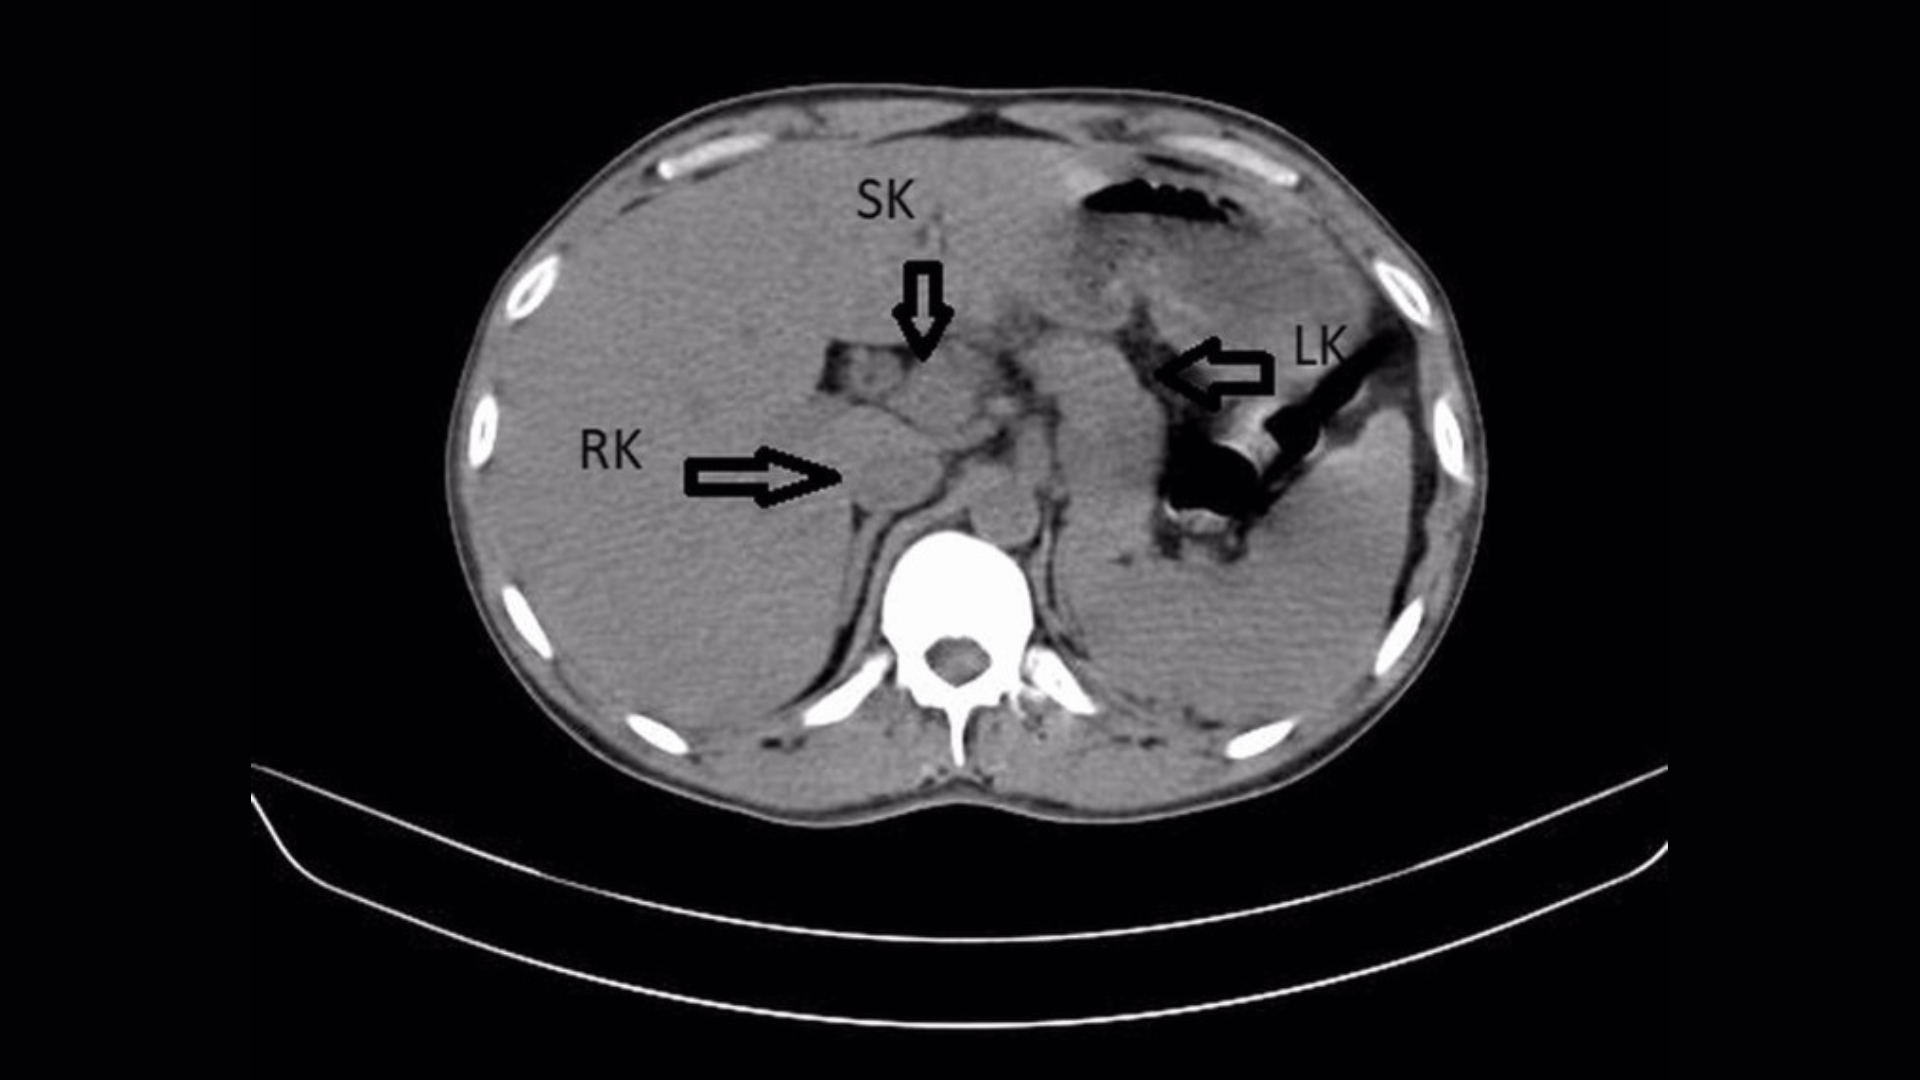

Diagnostisches Dilemma: Rückenschmerzen eines Mannes führten zur Entdeckung einer dritten Niere: Bei einem Mann, der wegen einer Harnwegsinfektion behandelt wurde, stellte sich heraus, dass er eine seltene „überzählige Niere“ hatte.